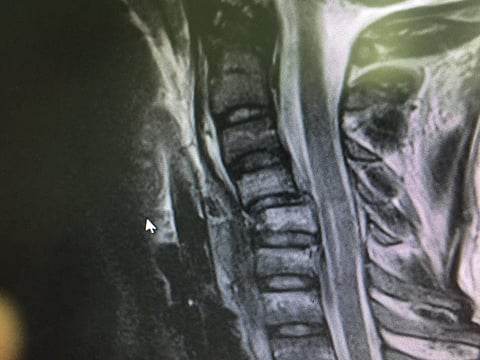

وخضع المريض لعدد من الفحوصات المخبرية والإشعاعية، شَمِلَت التصوير بالرنين المغناطيسي (MRI)، والتصوير الطبقي المقطعي (CT.SCAN)، إضافة إلى عدد من الفحوصات العصبية لتخطيط الدماغ.

وأجريت العملية بشكل طارئ، واستمرت لمدة ثلاث ساعات تم خلالها تثبيت الفقرات العنقية بالصفائح والمسامير، وإزالة الفقرة المكسورة، وكذلك إزالة الضغط عن الحبل الشوكي العنقي، مع زراعة عظم من حوض المريض بدلاً عن الفقرة المكسورة، وقد تكللت العملية بالنجاح ولله الحمد.